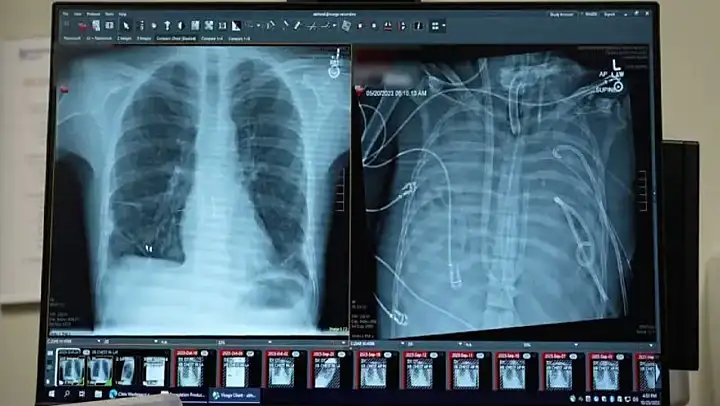

Cerrahlar, akciğerleri geri dönüşü olmayan şekilde hasar gören bir hastayı, organ nakli yapılana kadar yapay akciğer sistemiyle 48 saat boyunca hayatta tutmayı başardı.

Tıp dergisi Med'de 29 Ocak'ta yayımlanan çalışmaya göre, doktorlar kanı oksijenlendiren ve kalp dolaşımını destekleyen şantlar, tüpler ve pompalarla özel bir sistem geliştirdi. Uzmanlar, bunun gerçek anlamda bir yapay akciğerin, uygun donör bulunana kadar hastayı yaşatabileceğini gösterdiğini belirtiyor.

Bunun üzerine cerrahlar, hastanın hastalıklı akciğerlerini tamamen çıkararak geliştirdikleri yapay akciğer sistemine bağladı. Sistem, kalbin sağ tarafından alınan kanı bir pompadan geçirerek oksijen ekliyor ve karbondioksiti uzaklaştırıyor, ardından kanı kalbin sol tarafına yönlendirerek vücuda pompalanmasını sağlıyor. Böylece hem kalbin normal işlevi korunuyor hem de dokulara oksijen ulaştırılıyor.

Daha önce doktorlar, ekstrakorporeal membran oksijenasyonu (ECMO) adı verilen dış destek sistemini kullanarak, nakil bekleyen bazı hastaları akciğersiz olarak hayatta tutmuştu. Ancak Bharat, ECMO'nun kalp için yeterli kan akışını sağlamadığı için gerçek anlamda bir yapay akciğer olmadığını ifade etti.